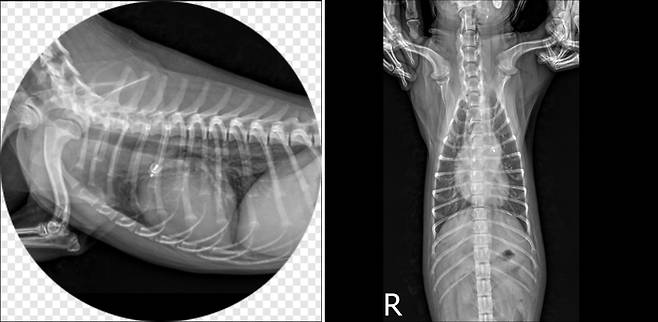

29일 SD동물의료센터(에스디동물의료센터)에 따르면, 최근 생후 6개월 된 암컷 말티푸 '코코(가명)'는 최근 중성화 수술을 위해 병원을 찾았다. 수술 전 마취가 가능한 상태인지 확인하기 위해 신체검사와 혈액검사, 흉부 방사선 촬영을 진행하던 중 예상치 못한 이상 소견이 발견됐다. 청진 과정에서 강한 심 잡음이 확인된 것이다.

보호자는 "평소 숨이 조금 빠르고 산책하면 쉽게 지치는 편이었지만, 그냥 활발한 성격 때문이라고 생각했다"고 말했다. 그러나 정밀 심장초음파 결과 코코는 선천성 심장질환인 동맥관개존증(PDA)을 앓고 있는 것으로 진단됐다. PDA는 태어나면서 자연스럽게 닫혀야 하는 혈관이 열려 있는 상태로 남아 심장에 지속적인 부담을 주는 선천성 심장질환이다.

김규창 SD동물의료센터 외과 원장은 "보호자가 느꼈던 빠른 호흡, 피로, 간헐적 기침은 PDA에서 흔히 나타나는 전형적인 임상 증상"이라며 "보호자와 충분히 상의한 뒤 한 번의 마취로 중성화 수술과 PDA 중재적 시술을 동시에 진행했다"고 설명했다.

수의계에 따르면 과거에는 PDA가 진단되면 개흉 수술이 주된 치료 방식이었다. 최근에는 흉부를 절개하지 않고 카테터를 이용해 진행하는 중재적 시술(interventional PDA closure)이 가능해졌다. 이 방법은 수술 부담을 줄이고 회복 속도를 크게 앞당길 수 있어 보호자와 동물 모두에게 도움이 된다. 코코 역시 하루 만에 퇴원할 수 있었다.